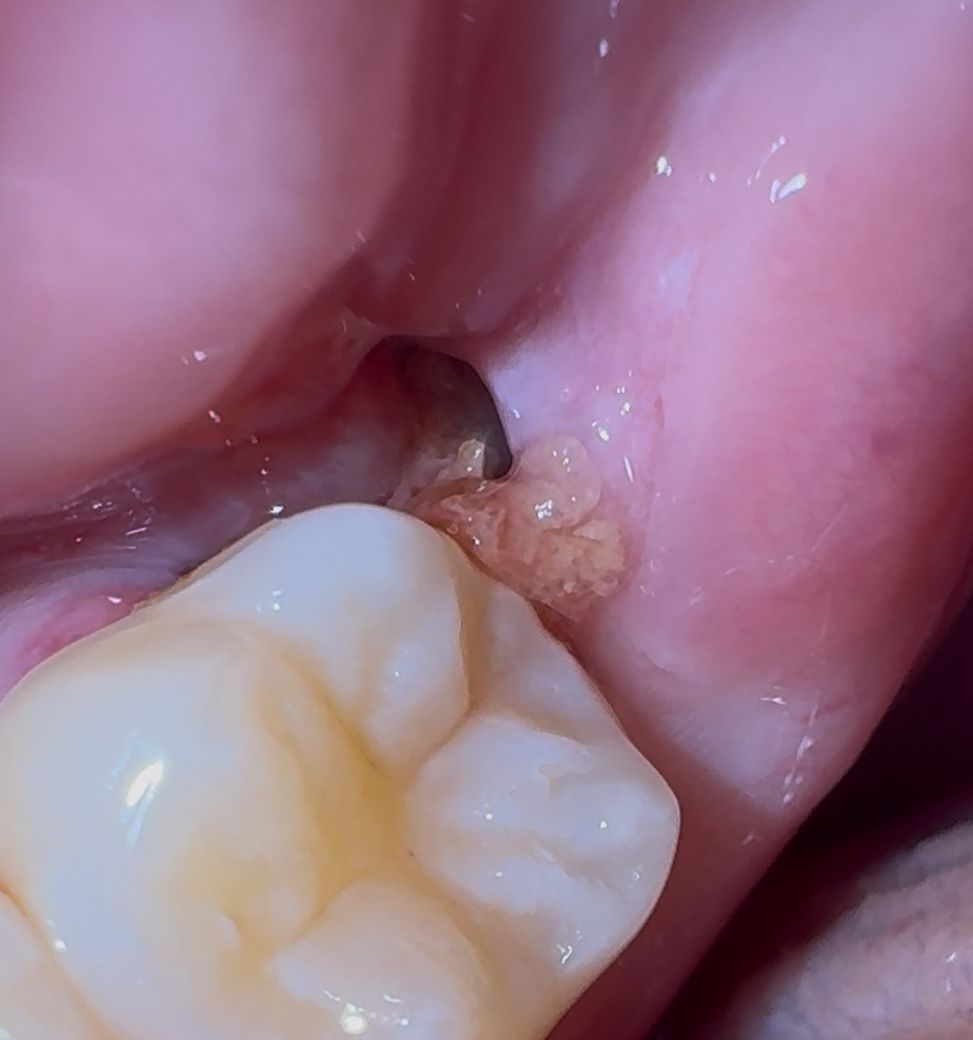

사랑니 발치 8일차입니다. 상태 어떤가요?

수평매복사랑니 뽑고 8일차입니다. 오늘 실밥 풀었는데 실밥 풀고 난 후 가끔씩 살짝 피맛 나네요

현재 저런 상태인데 괜찮은걸까요?

• 1번 째 사진

아직 잇몸이 다 아물지 않아서 그럴수도 있습니다. 음식물이 남아 잇지 않도록 식사를 하고나서 물로 여러번 헹구시는게 좋습니다.

사랑니 발치 후 8일 째라면 특별히 문제는 없어보이며 지금처럼 관리 잘 해주시면 되겠습니다.

사랑니를 발치하고 나면 발치한 부위에 구멍이 있을수 있습니다. 이런 구멍은 시간이 지나면서 점차 메꿔지게 됩니다.

실밥 풀고 잇몸이 다소 자극되어서 또 피가 일시적으로 조금 날 순 있습니다 사진상 상태 괜찮습니다